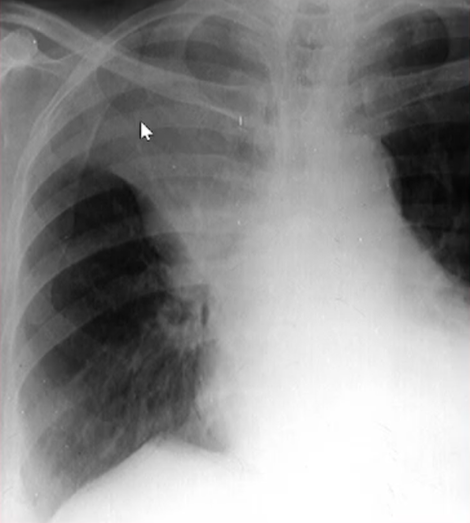

Rx toracică, incidență P-A

DESCRIERE:

la niv. întregului hemitorace drept → opacitate extinsă, nesistematizată, de intensitate mare, omogenă

caracter expansiv → împinge traheea și mediastinul de partea opusă

diafragm deplasat în jos

lărgirea spațiilor intercostale

umplerea spațiului costo-diafragmatic

DX: pleurezie masivă

DD: atelectazie → caracter retractil